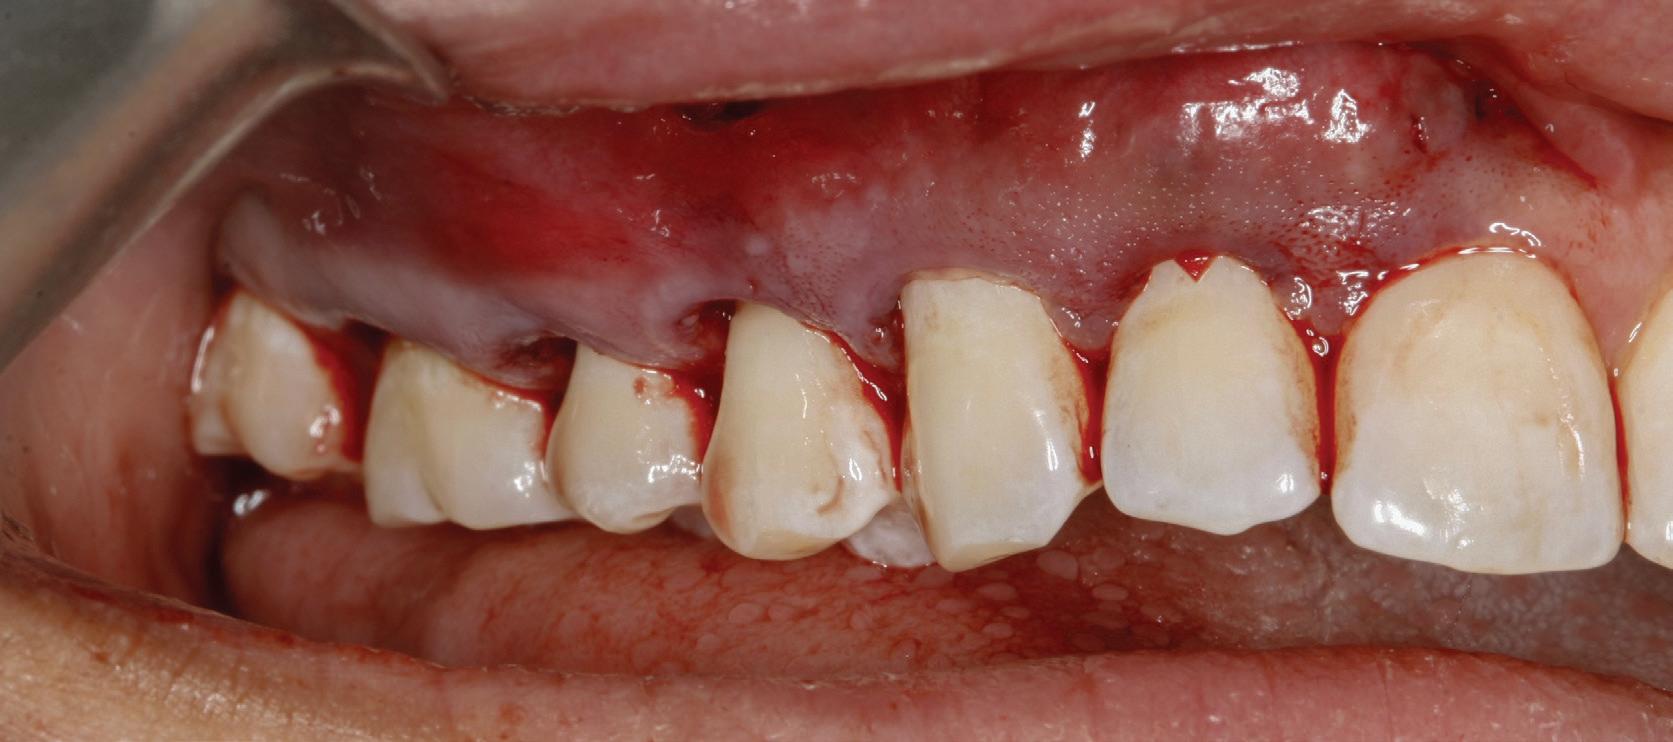

Planul de tratament a început cu accent pe restabilirea sănătății parodontale. Într-o ședință ulterioară, odată cu îmbunătățirea stării parodonțiului, s-a efectuat restaurarea molarului nr. 46. Sub anestezie la Spina Spix pe partea dreaptă și

Figurile:

3. Cavitate de clasa a II-a preparată.

4. Septomatrix pe poziție.

5. Cavitatea profundă.

izolarea cu digă de cauciuc, restaurarea din amalgam a fost îndepărtată complet și s-a obținut accesul la cavitatea carioasă (fig. 3-5). În ciuda proximității față de țesutul pulpar, nu a avut loc nicio expunere, iar cavitatea de clasa a II-a a fost restaurată complet cu Biodentine™ (fig. 6-8).